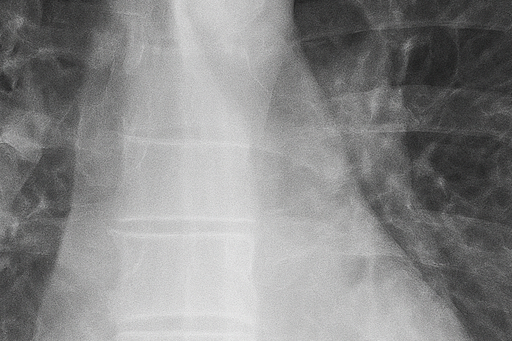

(2) 흉부 X선 검사

흉부 X선 촬영은 가장 기본적이고 신속한 진단 방법입니다. X선 영상에서 공기가 찬 부위는 검게 보이며, 허탈된 폐는 중심 쪽으로 쪼그라든 형태로 나타납니다. 이를 통해 폐 허탈의 범위와 기흉의 크기를 확인할 수 있습니다. 그러나 폐 상부의 작은 공기집(bleb)은 X선으로 잘 보이지 않아, 필요한 경우 흉부 CT 검사를 시행합니다.